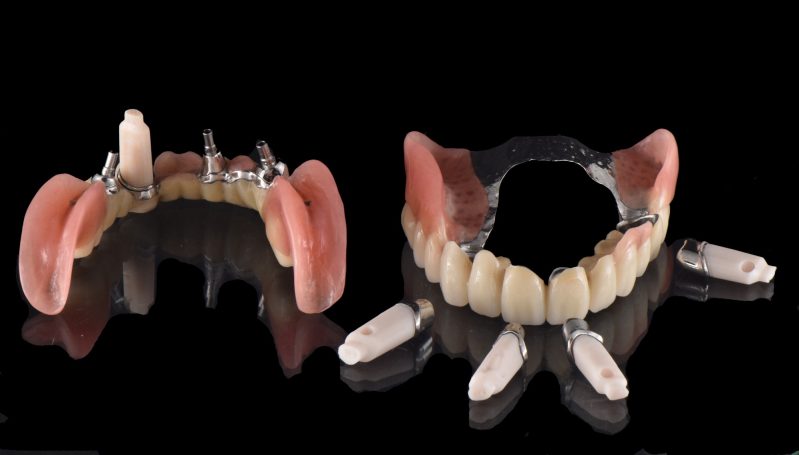

Verschraubte Implantatbrücken fühlen sich für den Patienten an wie die eigenen Zähne.

Implantsteg verankerte Brücke. Für den Patienten abnehmbar, aber der Tragekomfort von festen Zähnen.